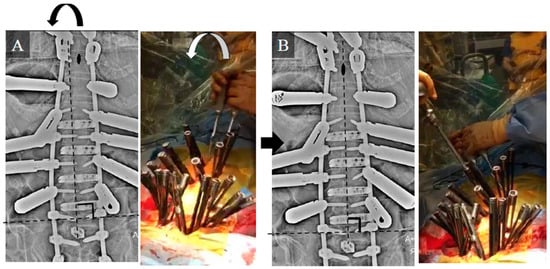

3.1. Case Study 1: RR

3.2. Case Study 2: RR and SD

3.3. Case Study 3: RR and KR